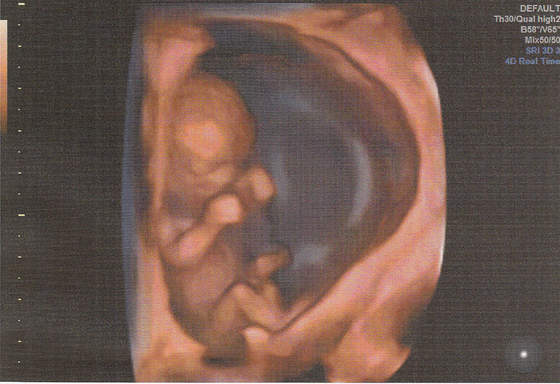

Hej ja po wizycie, bąbel młodszy o 2 dni niz z OM wiec mam sie za tydz pokazac na przeziernosc. Reszta ok, raczki, nozki, zoladek itd itd. Maluch ma 4,84 cm. Ja w pt ide na dokladne usg to moze cosik sie uda podgladnac a na razie taka tylko fotka na szybko. Tak sie wiercil maluch ze nie mozna bylo zrobic ladnego zdjecia